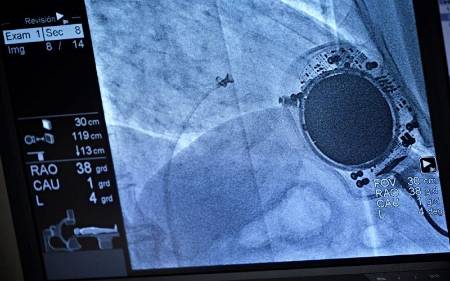

Primero, se realiza una punción en la zona de la ingle que permite acceder y navegar por esta vena hasta alcanzar el corazón. Para conseguirlo, se utilizan imágenes reales y en movimiento desde la sala de hemodinámica.